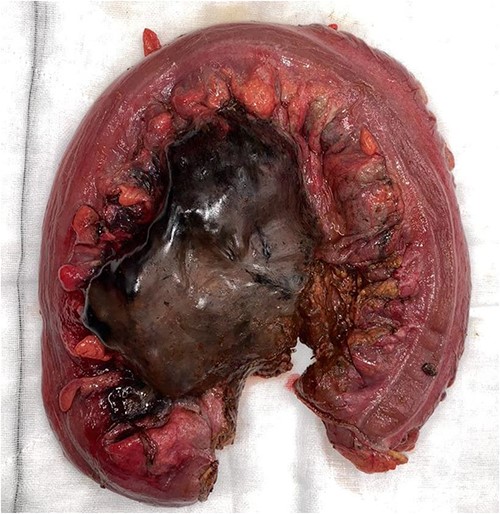

On CT of her abdomen and pelvis, there was a large volume of pneumoperitoneum and a massive sigmoid faecaloma suggestive of stercoral perforation associated with ischaemic changes (Fig. 1). She underwent emergency laparotomy, which identified a grossly dilated and redundant sigmoid colon impacted with a large, inspissated faecaloma >15 cm in diameter (see Figs 2 and 3). The perforation was identified in the mid to distal sigmoid colon with evidence of necrosis of the wall. A Hartmann’s procedure and extensive washout was performed. Post-operatively, the patient required vasopressor support for septic shock in intensive care, as well as granulocyte colony stimulating factor (G-CSF) to help in the management of her febrile neutropaenia. Her Clozapine was suspended for several days due to her neutropenia. She was given G-CSF to improve her neutropenia to improve her chances of survival as it known that immunocompromised patients with sepsis have worse prognosis [9]. Fortunately, the patient recovered well post-operatively and was discharged to rehabilitation on day 10.

Intraoperative findings of ischaemic stercoral perforation of the sigmoid colon.